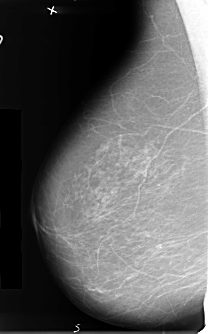

B_3412_1.LEFT_MLO

LEFT_MLO LINES 4816 PIXELS_PER_LINE 2728 BITS_PER_PIXEL 12 RESOLUTION 50 OVERLAY

FILE: B_3412_1.LEFT_MLO.OVERLAY

TOTAL_ABNORMALITIES 1

ABNORMALITY 1

LESION_TYPE MASS SHAPE ROUND-IRREGULAR-ARCHITECTURAL_DISTORTION MARGINS SPICULATED

ASSESSMENT 5

SUBTLETY 5

PATHOLOGY MALIGNANT

TOTAL_OUTLINES 1

BOUNDARY